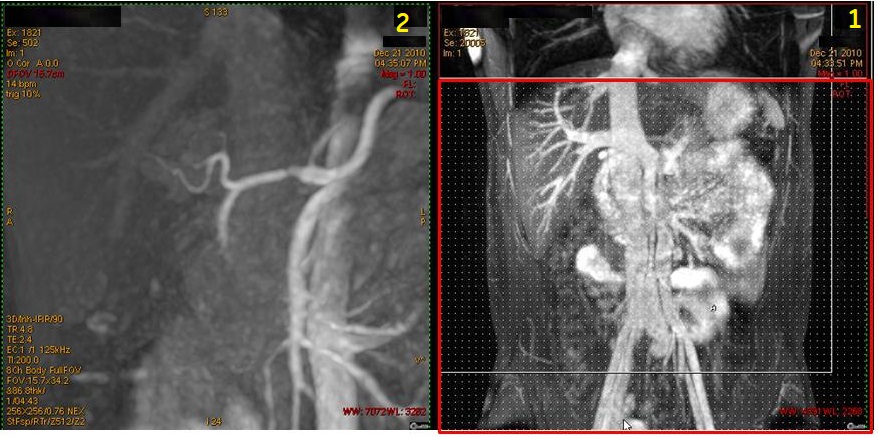

Figure 8. Coronal localizer with IR band and resultant coronal abdominal veins

Table 6. Image legend

NumberDescription

1Coronal localizer with axial IR band (red box) applied over the heart to saturate arterial flow.

2Resultant Inhance Inflow IR coronal image of abdominal veins.